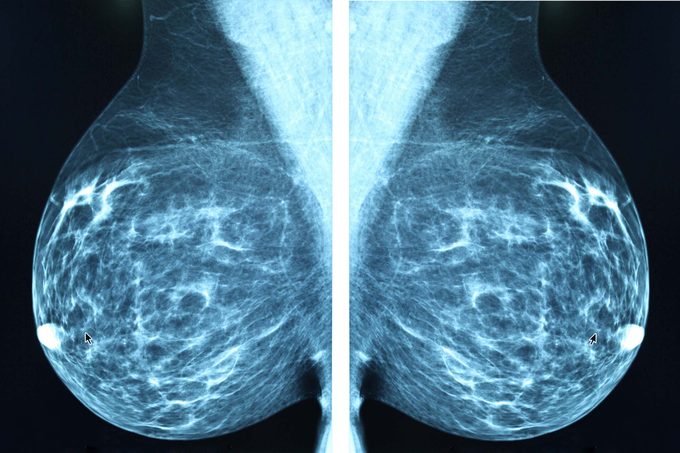

You have dense breasts

Dense breast tissue is quite common, and researchers have unfortunately linked it to an increased risk of larger tumors or more advanced cancer at diagnosis. Dense breast tissue can make it more difficult to detect problems on a mammogram, which is why women at high risk and/or with dense breasts may benefit from a more sensitive test: breast MRI. “Unfortunately, we’ve seen women skip their MRI and then get diagnosed down the road,” says Dr. Elliott. “We always wonder if it could have been caught earlier and if they could have avoided chemotherapy.” These are the foods cancer docs warn against eating.